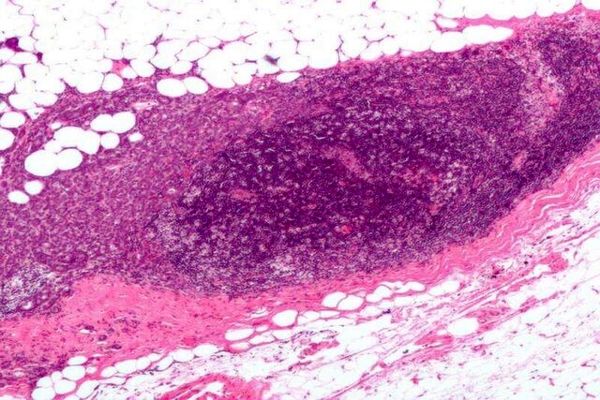

مطالعهای جدید که به بررسی سطوح آنتیاکسیدان و نشانگرهای استرس در خون پرداخته میتواند به ایجاد روشی جدید برای تشخیص…

نتایج نشان داد شرکت کنندگانی که در این آزمایش دوز بالاتری از امگا ۳ مصرف کرده بودند، در طول تست آسیب کمتری از استرس به…